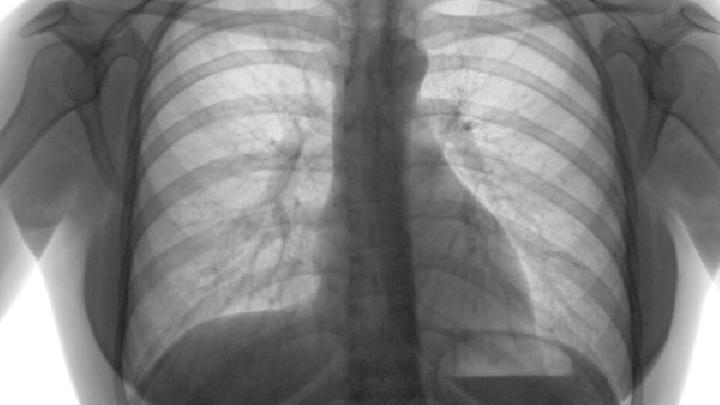

晚期肺气肿、肺感染或肺结核。并发症包括咳嗽、气短和胸闷,伴有全身疲劳。当支气管和肺部感染合并时,咳痰和发烧。肺部听到干湿的声音。鼻腔干燥,鼻毛脱落,鼻粘膜和咽部充血,鼻甲肥大。早期肺功能损伤较轻,主要是阻塞性或限制性通风功能障碍。由于肺容积的缩小,主要是限制性或混合性通风功能障碍,伴有通风功能障碍。严重时,肺部反复感染,呼吸衰竭死亡。